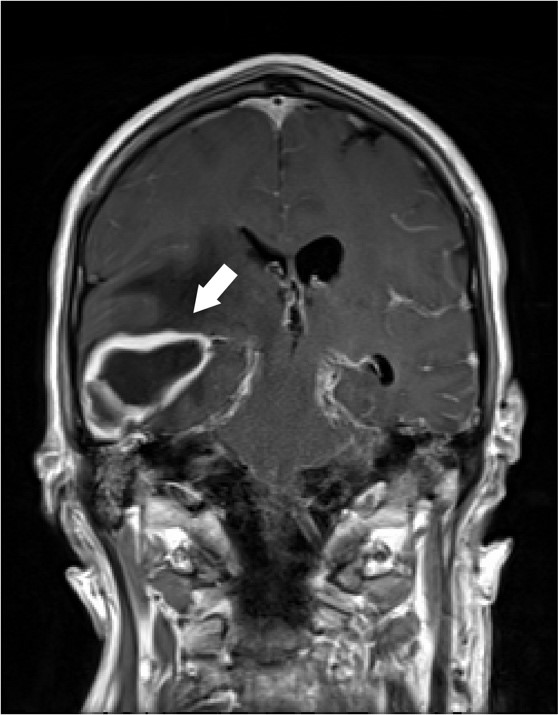

A 62 year old male with unknown past medical history was dropped off at the emergency department by EMS after being found altered with concern for IV drug use. On presentation he was febrile to 104.5o F, tachycardic, and although he was initially responsive, his mental status deteriorated. Labs were drawn and broad-spectrum antibiotic coverage with vancomycin, cefepime, and metronidazole was initiated in the ED. He then had a tonic-clonic seizure event and was given intravenous levetiracetam. A CT brain showed a right inferior temporal lobe lesion, initially interpreted as likely glioblastoma multiforme, causing subfalcine and uncal herniation. MRI revealed a ring-enhancing mass measuring 3 cm x 3 cm x 3 cm in the right temporal lobe with significant surrounding edema. CT of the temporal bones also revealed right mastoiditis (Figures 1 and 2).

Figure 1. Coronal T1 post-contrast MRI demonstrating the ring-enhancing mass in the right temporal lobe (arrow).